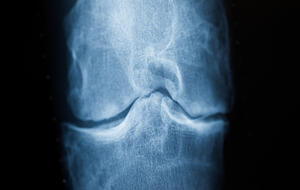

Mythos 3: Wer oft hockt, macht sein Knie kaputt und bekommt Arthrose.

Ist die Hocke wirklich schlecht fürs Knie? Wer oft auf den Knien herumrutscht, bekommt häufig Arthrose in den Kniegelenken. „Das ist falsch“, sagt Johannes Beckmann, Chefarzt an der Sportklinik in Stuttgart. Schleimbeutelentzündung durch Überreizung – ja. Aber die Gelenke gehen nicht automatisch kaputt, wenn man hockt oder kniet. Sonst hätten Menschen in Asien oder dem arabischen Kulturkreis alle Arthrose. „Das ist aber in erster Linie eine Erkrankung der Industrienationen“, sagt Beckmann.

Wodurch Arthrose begünstigt wird

Sie wird begünstigt durch Übergewicht, wenig Bewegung, schlechte Ernährung. Weitere Ursachen: erbliche Veranlagung, (Sport-)Unfälle oder Verletzungen sowie eine starke Fehlstellung des Kniegelenks, zum Beispiel O-Beine. Diese kann zu einer ungleichmäßigen Belastung führen und so den Abbau des Knorpels, der als eine Art Stoßdämpfer zwischen den Gelenken dient, beschleunigen.